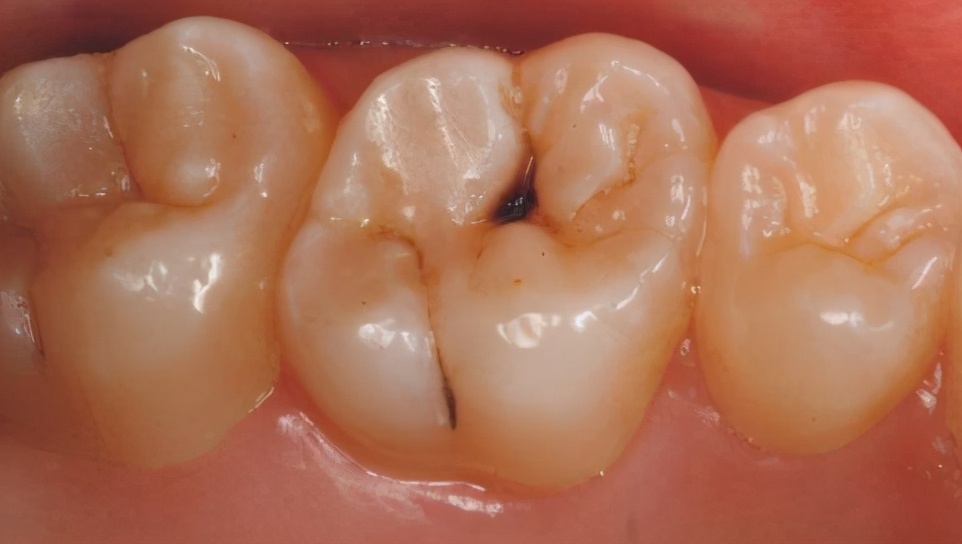

如果是蛀牙,任由小黑点继续发展的话会演变成明显的龋洞;久而久之,牙齿接触到冷热酸甜等食物会有刺激敏感,当损伤进一步到达牙髓(即“牙神经”)时,会疼痛难忍,尤其是夜间想睡个好觉都难!

但,生活中很多人都会习惯性拖延,牙齿出现问题不疼就不关,非得等到牙痛得受不了,才到医院就诊。这时可能单纯的补牙已经无法治疗了,可能还要做根管治疗甚至拔除患牙、进行假牙修复,费时费力又费钱,人还遭罪。这就是所谓的“小洞不补,大洞吃苦”。